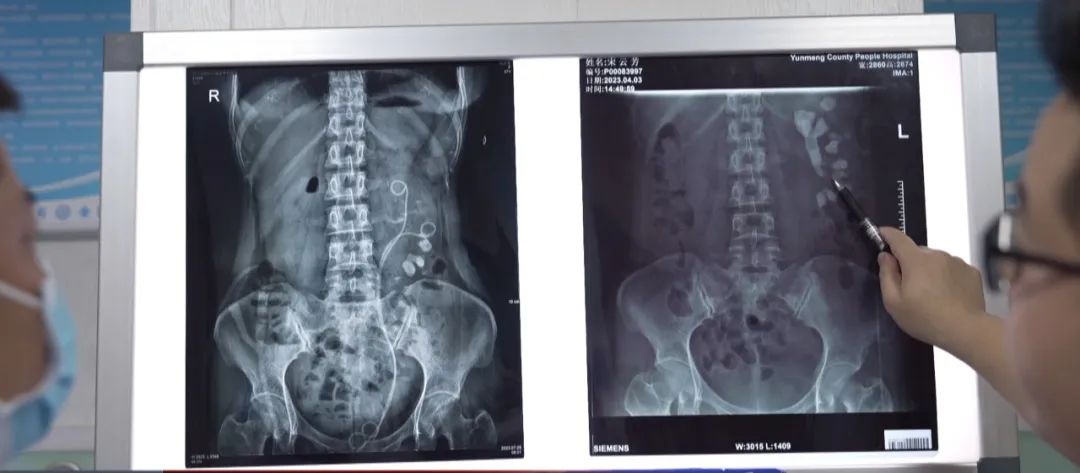

據(jù)說, 腎結(jié)石會痛到懷疑人生。 但很少有人知道, 夏季氣溫飆升 會增加患腎結(jié)石的風險。 腎結(jié)石的成因很多,往往是存在一種或多種影響結(jié)石形成的因素,包括年齡、性別、種族、遺傳、環(huán)境因素、飲食習慣、職業(yè)等。 最近,來自湖南的宋女士,過的是相當?shù)挠魫。她的左腎里“不聲不響”的長了顆10公分的“珊瑚”結(jié)石,左腎還差點沒了。宋女士這兩個月內(nèi)四處求醫(yī),做了三次打洞取石手術(shù),卻仍然無法將結(jié)石完全清除。 “左腎里邊結(jié)石都長滿了,太嚇人了!”原來,檢查結(jié)果顯示,宋女士是左腎多發(fā)結(jié)石伴積水,結(jié)石最大直徑約10公分,其形狀猶如海底珊瑚,填滿了整個左腎盂和所有腎盞腔隙,腎臟功能已出現(xiàn)了嚴重損傷。醫(yī)生告訴宋女士,如果再不及時治療,腎臟功能將會持續(xù)受損乃至完全喪失,到時候就只能切腎了。 結(jié)石形成可能與這幾個因素有直接關(guān)系。第一,她的左腎先天畸形,存在腎臟旋轉(zhuǎn)不良、盞頸口狹窄等問題。 第二,由于結(jié)石在體內(nèi)長期不處理,持續(xù)損傷腎臟功能,導致了腎盂與輸尿管交界處嚴重狹窄、變形;同時還導致了多個小盞頸口的狹窄與閉鎖。這幾個情況都會直接影響腎臟的尿液引流不暢,造成腎臟積水的發(fā)生,給結(jié)石的形成與瘋長創(chuàng)造有利條件。 第三,宋女士存在長期的泌尿系感染,這會加劇結(jié)石瘋長。根據(jù)術(shù)后宋女士的結(jié)石成分分析,提示其為感染性結(jié)石,這也印證了這一結(jié)論。 醫(yī)生指出,腎結(jié)石如果產(chǎn)生了嚴重梗阻及繼發(fā)性感染,一般可出現(xiàn)鈍痛、脹痛等典型癥狀;如果結(jié)石掉入輸尿管里形成嵌頓,還會誘發(fā)劇烈腎絞痛、血尿等癥狀。 高溫、潮濕和缺乏水分,都會使腎結(jié)石的發(fā)病率升高。 天氣炎熱易患腎結(jié)石該如何避免呢? 多喝水,保持水分以稀釋尿液,如果以前有腎結(jié)石,則每天至少喝8杯水,12杯更好。 ★ 如果外面很熱并且出汗了,要多喝水。 ★ 在水中加入檸檬汁或酸橙汁,因為檸檬酸鹽與鈣結(jié)合,有助于阻止結(jié)石的形成。 ★ 限制鈉攝入量,高鈉飲食會增加尿液中的鈣含量,建議將鈉攝入量限制在每天2300毫克(相當于大約1茶匙)。 ★ 在飲食中減鹽也對腎臟有益,可幫助降低血壓。慢性高血壓會使血管變窄和變?nèi),影響血液流動,并可能導致腎臟疾病或衰竭。 ★ 吃富含鈣的食物。正常量的鈣對人體鈣調(diào)節(jié)至關(guān)重要,盡管這似乎違反直覺,因為鈣與腎結(jié)石的形成有關(guān)。但食物中的鈣與腸道中的草酸鹽結(jié)合,會迫使草酸鹽進入糞便而不是尿液,這樣可以降低患草酸鈣結(jié)石的風險。 ★ 每天從乳制品、大豆、豆類、強化豆腐和綠色蔬菜(羽衣甘藍和西蘭花是很好的來源)中攝入1000∽1200毫克的鈣。 ★ 多吃水果和蔬菜,可以幫助增加尿中的檸檬酸鹽,預防腎結(jié)石。 ★ 減少動物蛋白的攝入,因為動物蛋白會增加患結(jié)石的風險。動物蛋白不僅包括紅肉,還包括雞肉、魚,甚至雞蛋。Bollner建議將肉類攝入量限制在每天8盎司(約226.8克)。 ★ 即使是健康食物中的草酸鹽也會導致腎結(jié)石的形成,因此要監(jiān)控吃了多少這些食物:菠菜、甜菜、堅果、小麥胚芽、大黃和大豆等。單獨食用草酸鹽不太可能導致結(jié)石,但過量會大大增加風險。 ★ 保持飲食多樣化,或在食用草酸鹽含量高的食物時吃一份乳制品。